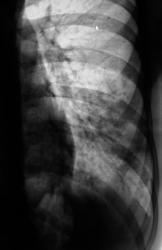

"Красивая" пневмония.

Пациент направлен на исследование врачом терапевтом с диагнозом "пневмония". Клиника пневмонии наличествует.

сегментарная пневмония (8 сегмент) с плевральным выпотом по глвной междолевой щели.